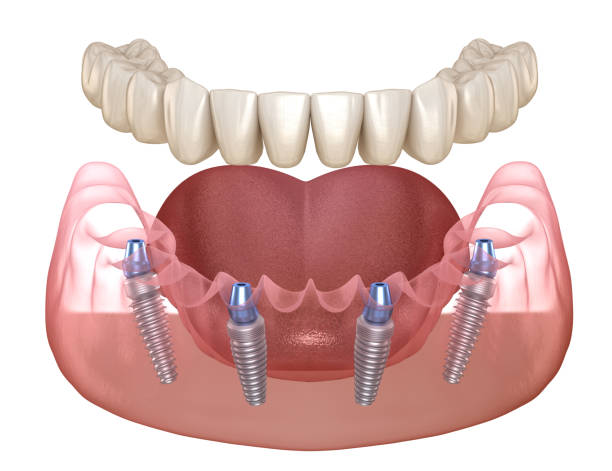

ایمپلنت یک روزه، همانطور که از نامش پیداست، روشی است که در آن کاشت ایمپلنت و نصب روکش دندان، در یک جلسه انجام میشود. در روشهای سنتی ایمپلنت، پس از کاشت ایمپلنت، باید چند ماه صبر کرد تا استخوان فک به ایمپلنت جوش بخورد (فرآیندی به نام استئواینتگریشن) و سپس روکش دندان نصب شود. اما در ایمپلنت یک روزه، این فرآیند تسریع شده و بیمار میتواند در همان روز کاشت ایمپلنت، دندان جدید خود را دریافت کند. برای درک بهتر نحوه عملکرد ایمپلنت یک روزه، مراحل زیر را در نظر بگیرید

- کاشت ایمپلنت در این مرحله، ایمپلنت (پایه تیتانیومی دندان) با استفاده از جراحی، در استخوان فک قرار داده میشود.

- نصب روکش دندان پس از کاشت ایمپلنت، روکش دندان (قسمت قابل مشاهده دندان) بر روی ایمپلنت نصب میشود. در ایمپلنت یک روزه، روکش دندان معمولاً به صورت موقت است و پس از چند ماه، با روکش دائمی جایگزین میشود.

- کاشت ایمپلنت در این مرحله، ایمپلنت با استفاده از جراحی، در استخوان فک قرار داده میشود. این عمل معمولاً تحت بیحسی موضعی انجام میشود.

- نصب روکش دندان پس از کاشت ایمپلنت، روکش دندان بر روی ایمپلنت نصب میشود. در ایمپلنت یک روزه، روکش دندان معمولاً به صورت موقت است و پس از چند ماه، با روکش دائمی جایگزین میشود.